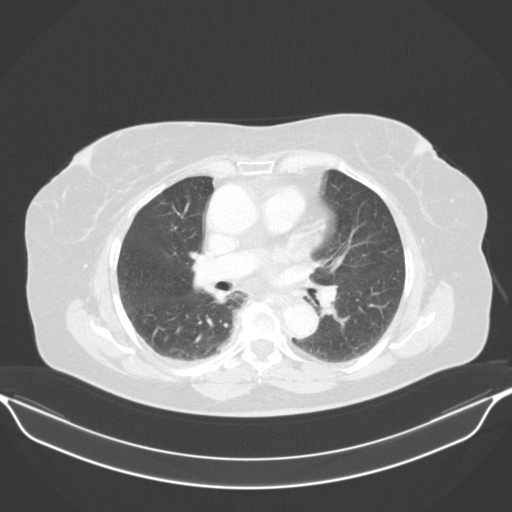

Image Grid

4Γ—3 grid: Rows show different image types (Original NATIVE, Reconstructed NATIVE, Original VENOUS, Generated VENOUS), Columns show windowing techniques (No Window, Lung Window, Mediastinum Window)

Original NATIVE CT scan (input)

No window - Raw intensity values

Reconstructed NATIVE CT scan (cycle consistency)

Original VENOUS CT scan

Generated VENOUS CT scan (A→B translation)